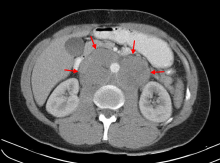

- Mesenteric lymphadenitis after viral systemic infection (particularly in the GALT in the appendix) can commonly present like appendicitis.[13][14]